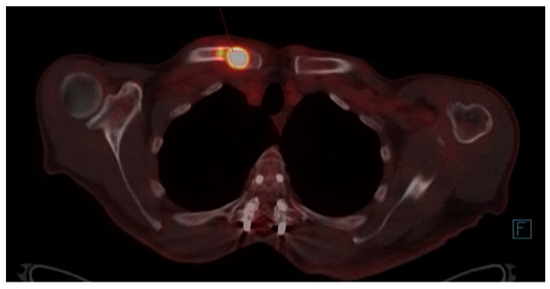

At this moment, the patient was offered (and accepted) to be enrolled in a clinical trial involving the use of single-agent Talquetamab, a bispecific antibody against CD3 and GPRC5D that redirects T cells to mediate the killing of GPRC5D-expressing myeloma cells. By the end of January 2023, after receiving eight cycles of Talquetamab, he achieved CR with no detectable residual disease in the bone marrow by Next-Generation Flow, and the examination by PET/TC showed a complete metabolic response in all the hypermetabolic lesions previously identified. Unfortunately, at the beginning of July 2023, before starting the 15th cycle of treatment, the patient complained again of bone pain in the right shoulder area. A follow-up PET/CT was requested, which showed a hypermetabolic lytic lesion (SUVmax = 7.7) located in the medial third of the right clavicle that was not presented previously and thus suggestive of progressive disease (Figure 2). At this point, no measurable disease was detectable in the serum or urine by SPEP/IFE or mass spectrometry.

Figure 2. Hypermetabolic lytic lesion (SUVmax = 7.7) in the medial third of the right clavicle, not present in the previous study and highly suggestive of progressive disease.